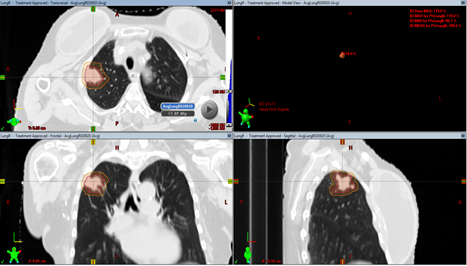

4、立体定向放射治疗(SBRT)

它是与剂量分割相关的放疗技术。这种技术就像是外科手术,通过精确定位放射源,将高剂量以单次或少量多次精确照射到肺癌病灶上,同时保护周围正常组织,从而达到治疗肺癌的效果。这种技术对于小病灶肺癌患者效果更佳,但需要高精度的影像学检查和能够精准递送辐射剂量的放射治疗设备。